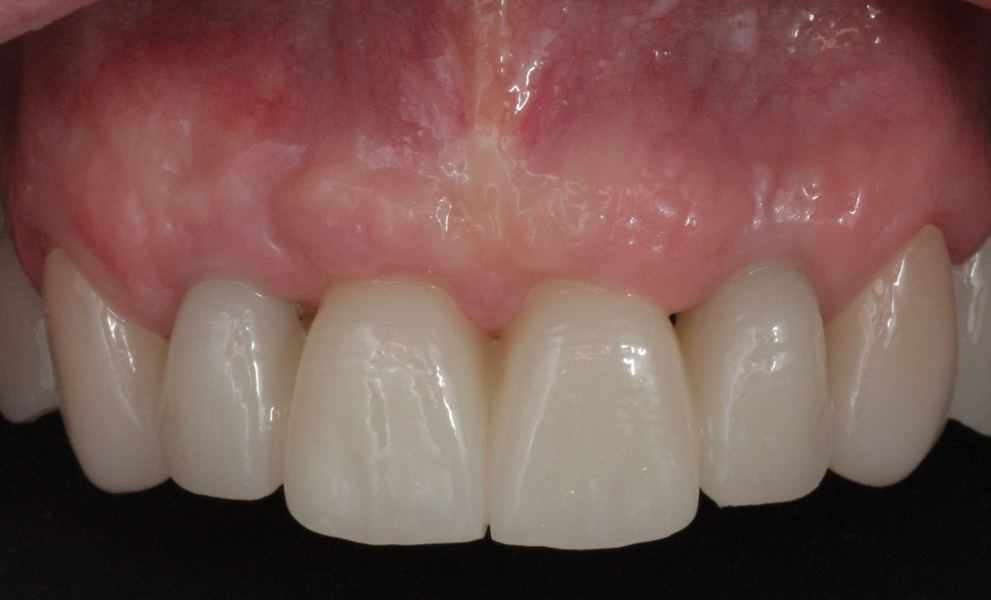

Definitive prosthetic treatment was performed after completion of implant healing with three CAD/CAM-fabricated monolithic zirconia bridges (DD cubeX2, Dental Direkt). The bridges were screwed on to BEGO titanium base abutments (Figs. 14–16). Good fit of the prosthetic superstructures was displayed in the radiograph after placement (Fig. 17). The two-year follow-up examination in July 2019 revealed excellent aesthetic and clinical soft-tissue conditions (Figs. 18–20). No radiographic bone loss had occurred at the implant sites (Fig. 21). Neither the submerged central incisors nor the distobuccal molar root displayed any signs of periapical inflammation, and the patient reported no complications. The patient’s oral hygiene had improved significantly during the follow-up period.

Fig. 18: Frontal aspect of the restorations after the two-year follow-up period.